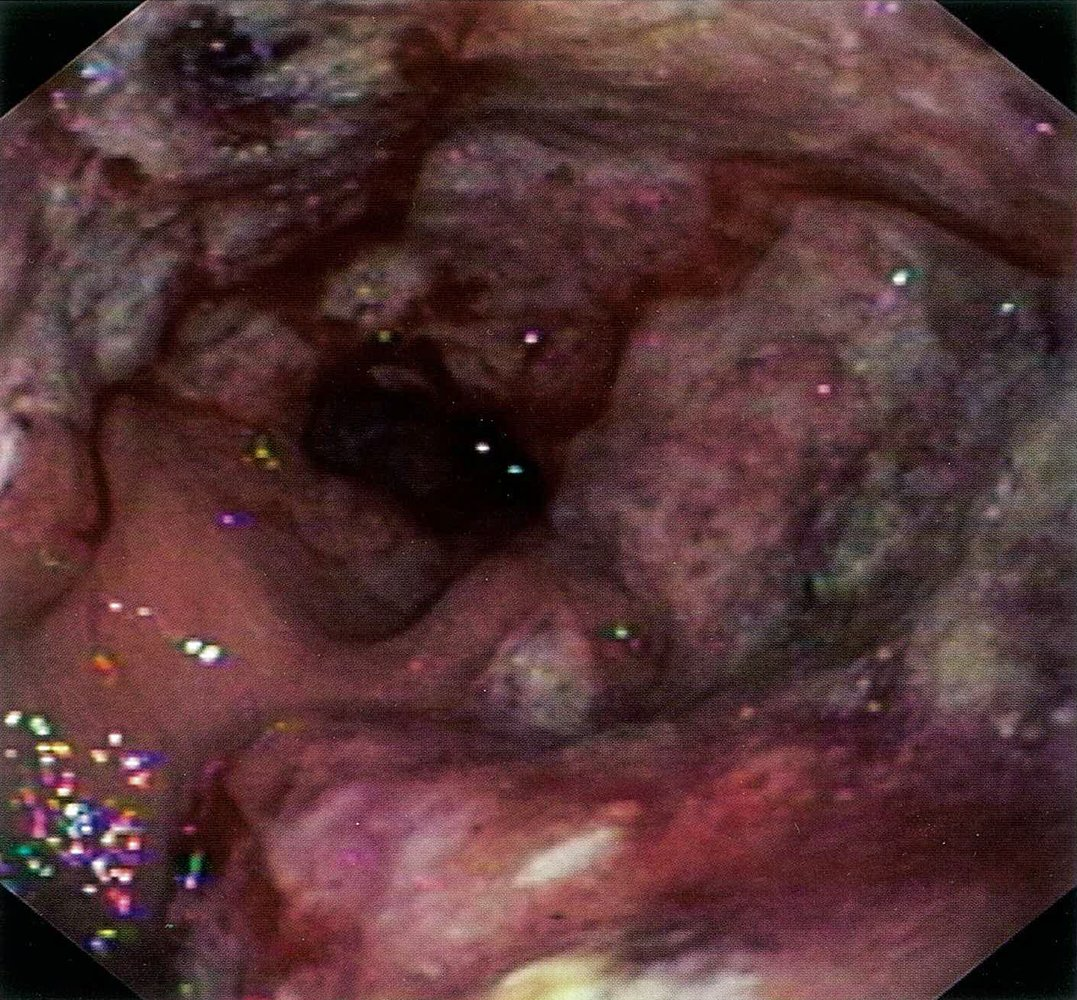

- Endoscopy

- Granulation tissue, ulcerations

- Thick infiltrates of small to medium-sized lymphoid cells